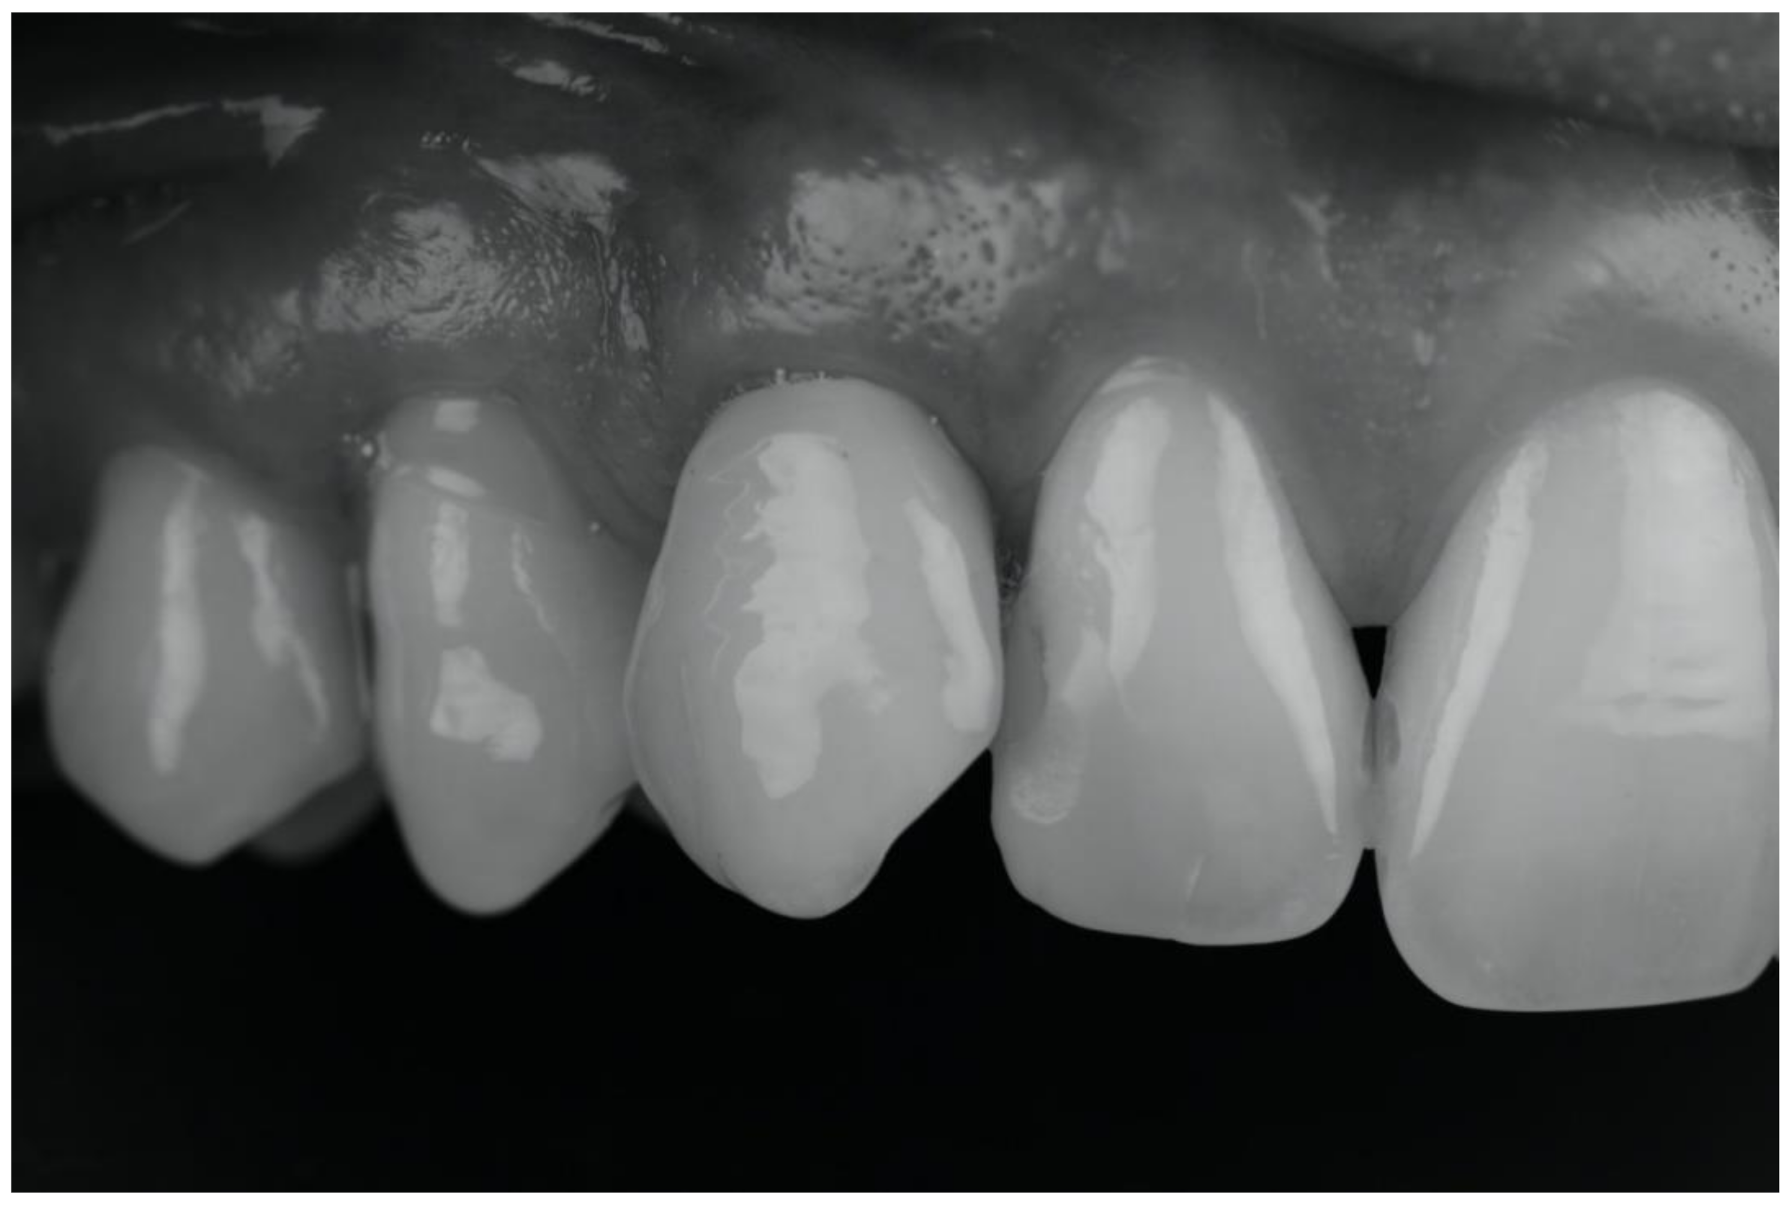

| (d) Removal of the deciduous tooth and replacement with implant-borne-prosthesis living in situ with the impacted canine, accepting the compromise of involving the impacted tooth in the implant seating procedure |

| (e) Surgical removal of the impacted canine and, in a second stage, removal of the deciduous tooth and replacement with implant-borne-prosthesis |